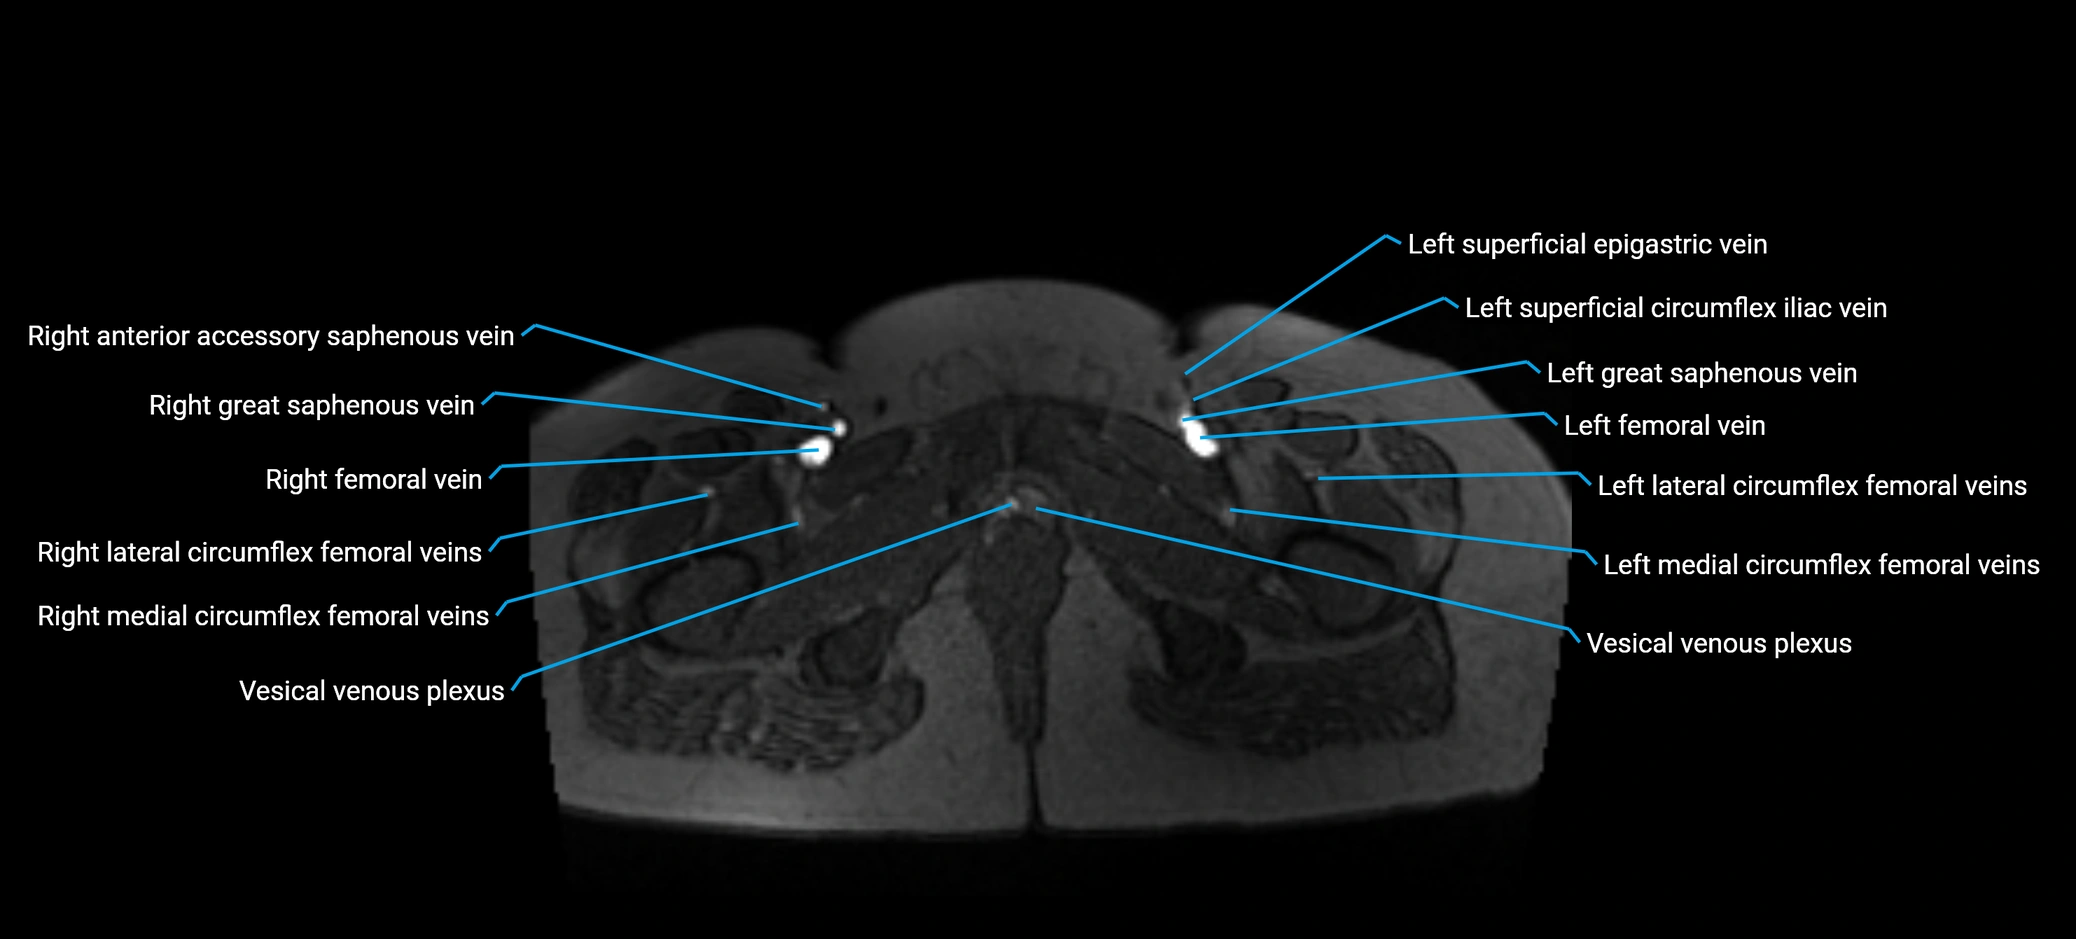

MRI image

image